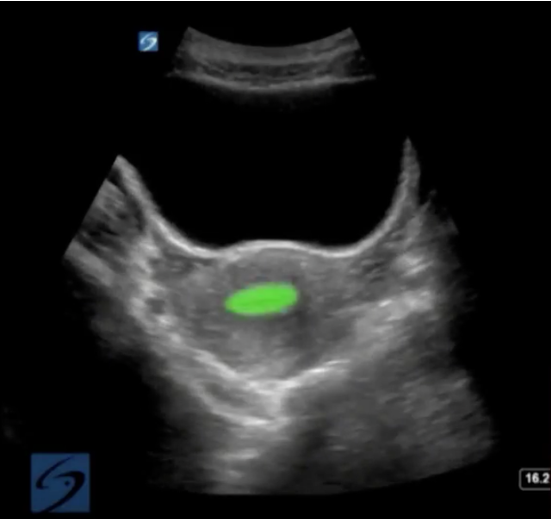

Pelvic Endometrium Highlighted Image

Highlighted Area: Endometrium